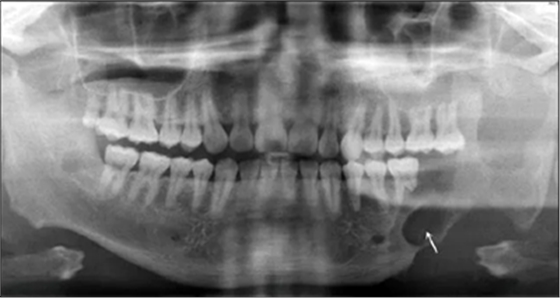

患者2014年6月5日因左下頜腫脹伴觸痛到青島大學(xué)附屬醫(yī)院口腔頜面外科就診,診斷為左側(cè)下頜骨成釉細(xì)胞瘤。全景片示左側(cè)下頜第二前磨牙遠(yuǎn)中至乙狀切跡處可見多房低密度影,左下頜第一磨牙遠(yuǎn)中根可見明顯吸收(圖1)。

2014年6月9日于本院行下頜骨左側(cè)成釉細(xì)胞瘤切除術(shù)+下頜骨節(jié)段性切除術(shù)+重建板重建術(shù)+血管化腓骨肌皮瓣轉(zhuǎn)移修復(fù)術(shù)+鈦板內(nèi)固定術(shù)+血管吻合術(shù)+牽引釘植入術(shù)+拔牙術(shù)(圖2)。

2016年3月22日復(fù)查,全景片示34~37牙缺失,左下頜單層腓骨移植,腓骨與下頜骨對(duì)接處骨愈合良好,鈦板鈦釘在位(圖3)。